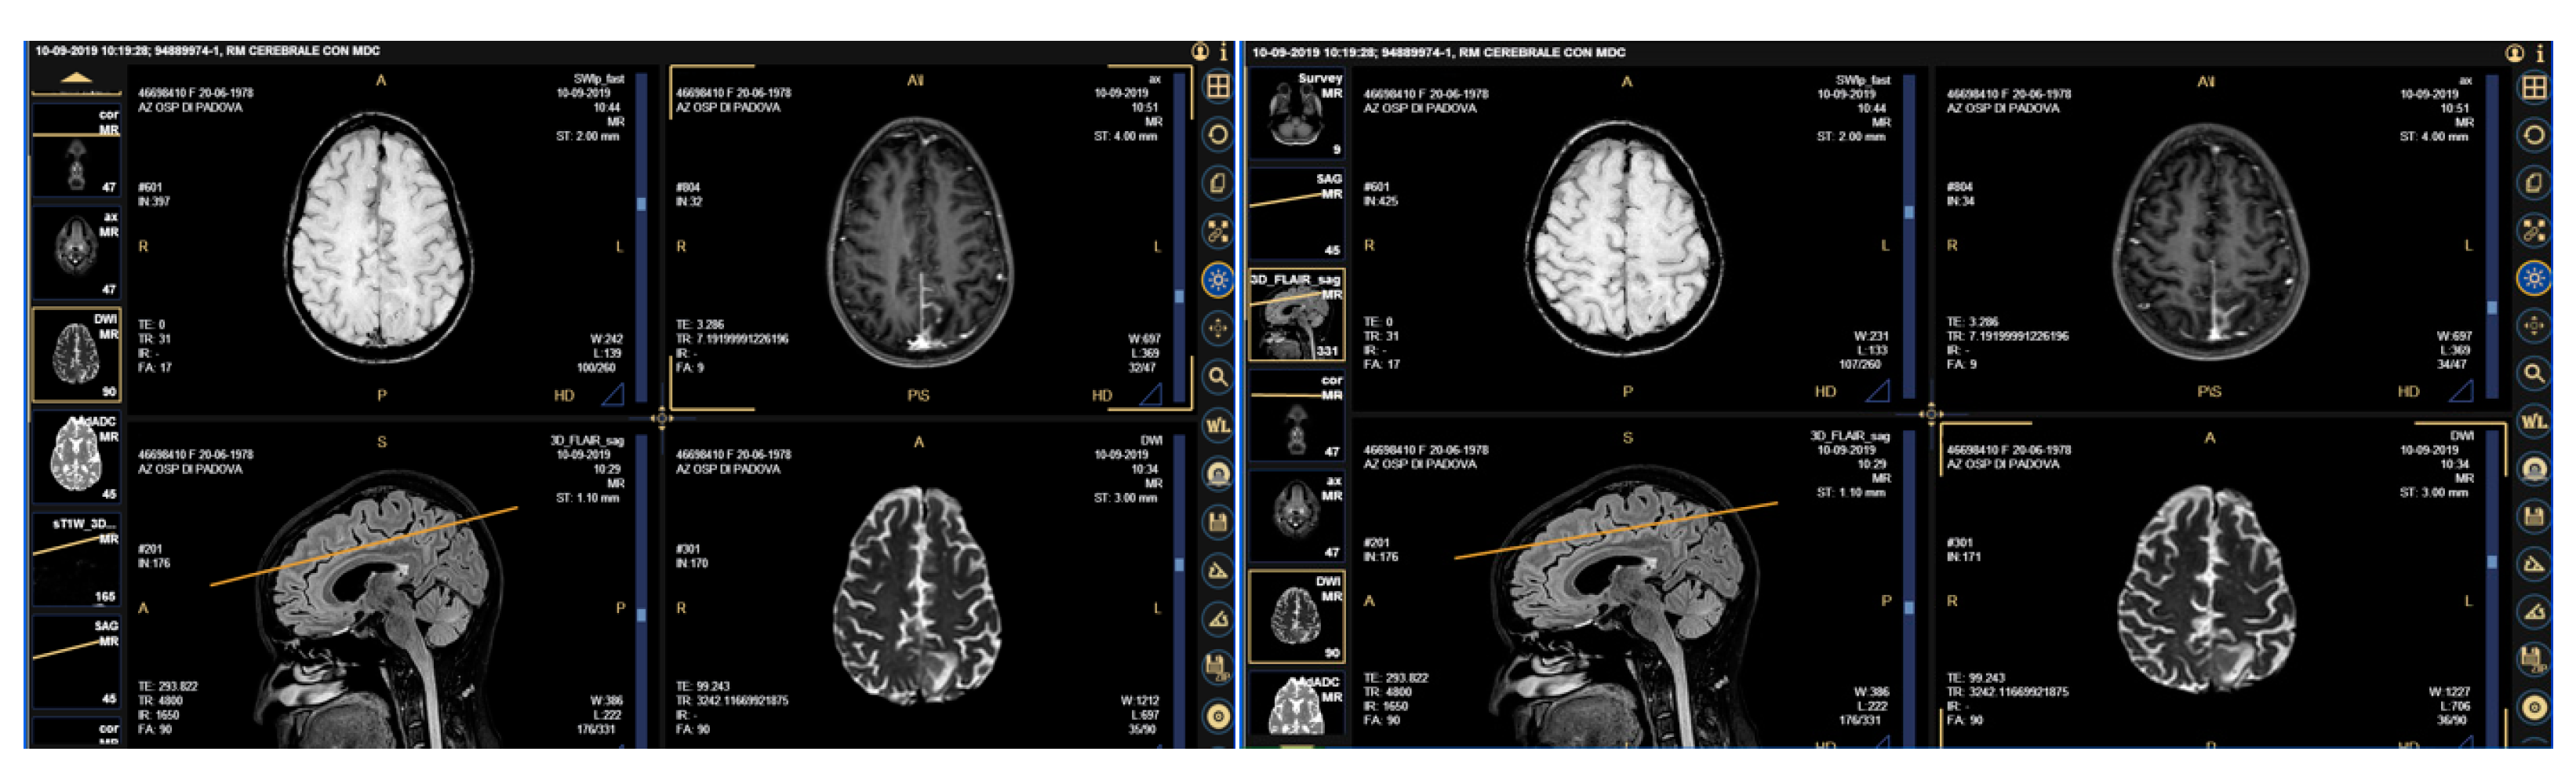

2.1. Case Presentation